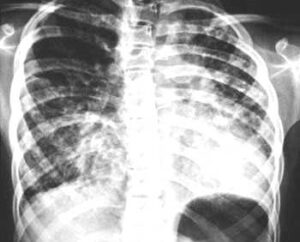

La fibrosis pulmonar se caracteriza por la inflamación de los pulmones y posterior cicatrización (fibrosis), condición que disminuye de manera gradual la capacidad respiratoria, provocando que los pacientes vivan con falta de aire constante, expresó la doctora Ivette Buendía Roldán, responsable del Laboratorio de Investigación Traslacional en Envejecimiento y Fibrosis Pulmonar del INER.

Si bien la fibrosis pulmonar es una enfermedad de baja prevalencia, cerca del 50% de los casos fallece de dos a tres años después de su diagnóstico, debido principalmente a la detección tardía, la cual limita la estrategia terapéutica y reduce el pronóstico de vida, aseveró la especialista.

Dada la complejidad de esta enfermedad, los pacientes suelen ser diagnosticados en estados avanzados, expuso el doctor Omar Barreto Rodríguez, coordinador de Atención Médica de Neumología adscrito a la Subdirección Médica del INER:

“Por lo que,para revertir esta tendencia, hay dos señales clave para sospechar de la existencia de fibrosis pulmonar, que es la aparición de tos crónica que persiste por más de ocho semanas sin responder a tratamientos comunes; y la falta de aire que va empeorando con el tiempo, donde los pacientes comienzan a cansarse al subir escaleras, luego al caminar rápido, e incluso pueden llegar al punto donde respirar se dificulta en estado de reposo”.